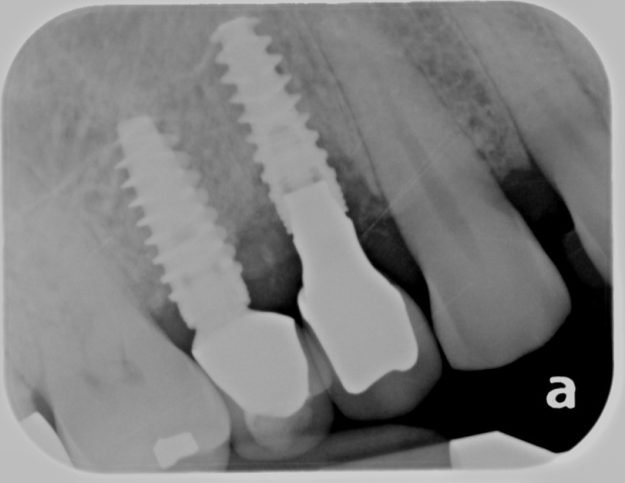

Missing teeth affect your smile, bite, and overall health. When possible, dental implants are the best tooth replacement option because they replace both the missing root and crown of the tooth. Fortunately, Adams and Cheek Dentistry offers implant services for our patients. What Is a Dental Implant? A dental implant is a titanium screw placed…